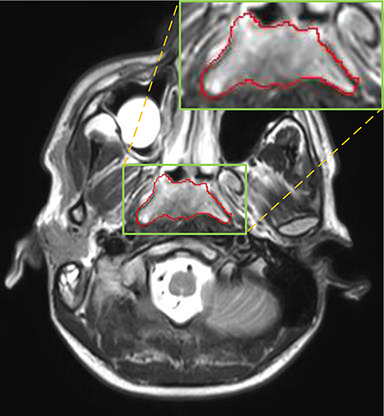

Currently, there is still no effort to fuse multi-modality MRI to develop an automatic segmentation system for NPC. According to researches of Popovtzer et al. [16], it should be a routine clinical practice to incorporate all kinds of MRI datasets in highly conformal radiation therapy to realize GTV delineation of NPC. For delineation of NPC, MRI is the perferred imaging modality for its superior soft tissue contrast [16, 3]. Moreover, MRI of different modalities data have different visual characteristics and various responses to different tissues and anatomical structures. For example, T1-weighted (T1) MRI is suitable for detecting skull base involvement and fat planes, while contrast-enhanced T1-weighted (CET1) MRI is used to identity tumor extent [3]. Figure 1 shows some examples of NPC response in T1, CET1 and T2-weighted (T2) MRI.

Refer to caption

Figure 1: Examples of slices from different MRI (T1, CET1 and T2), the contour of NPC is marked in red line. (a),(b) and (c) are slices from T1 , CET1 and T2 respectively.